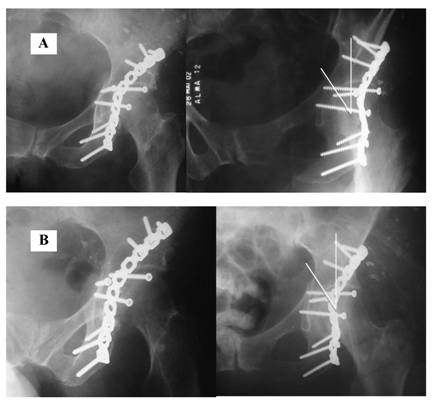

Figure 3

Immediate postoperative and last outclinic consultation radiographs of a patient (66.7 y/o female, road-traffic accident, unrestrained) without fixation of the anterior component of the transverse acetabular fracture. Roof-arc measurements didn't alter and the fracture healed uneventfully. After 56 months from the surgery, there are no signs of arthritis.

Except for the patient who had loss of articular reduction, the other 34 patients showed acetabular fracture healing at 12 weeks as shown by roentgenological examination. Post-operative reduction checked before patient discharge showed radiographic Matta angle superior to 45o in all cases of the current study. Radiographic roof-arc angles measured at three months postoperatively and at the last follow-up consultation didn't changed significantly (p > 0.05). There was no statistically significant difference between patients treated with and without fixation of the anterior component of the transverse acetabular fracture in terms of medial displacement of the femoral head (due to inadequate quadrilateral plate buttressing). Immediate post-operative and last follow-up consultation radiographs of a patient without anterior column fixation are demonstrated in Figure 3.